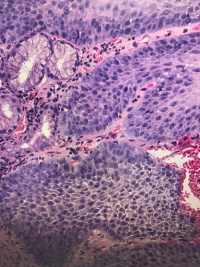

食道粘膜

腹痛,距门齿33cm处食管壁见0.4✖️0.5cm隆起

灰白组织一粒,直径0.1

鳞状上皮乳头状瘤性息肉,局部鳞状上皮轻度异型增生。

鳞状上皮下是幽门腺,胃粘膜异位

鳞上皮乳头上移,副基底层增生